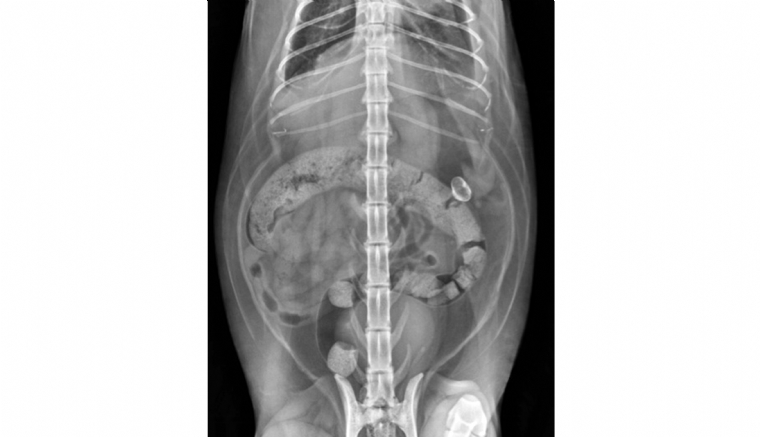

Mercredi 20 Avril 2022 Animaux de compagniePhoto n° 1A : Radiographie abdominale de face d'un chat présentant une structure minéralisée abdominale extra-digestive.v

Une chatte européenne, femelle stérilisée de 12 ans, est présentée pour des difficultés respiratoires évoluant depuis plusieurs jours.